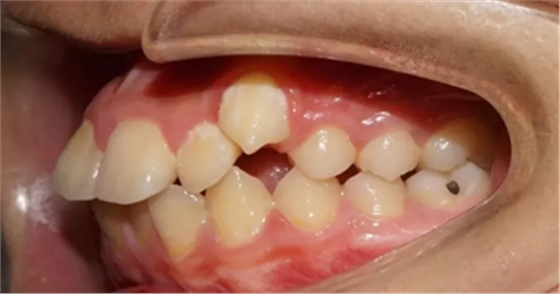

02 下頜后縮

因“沒有下巴”“臉型短”前來就診,該如何避免?